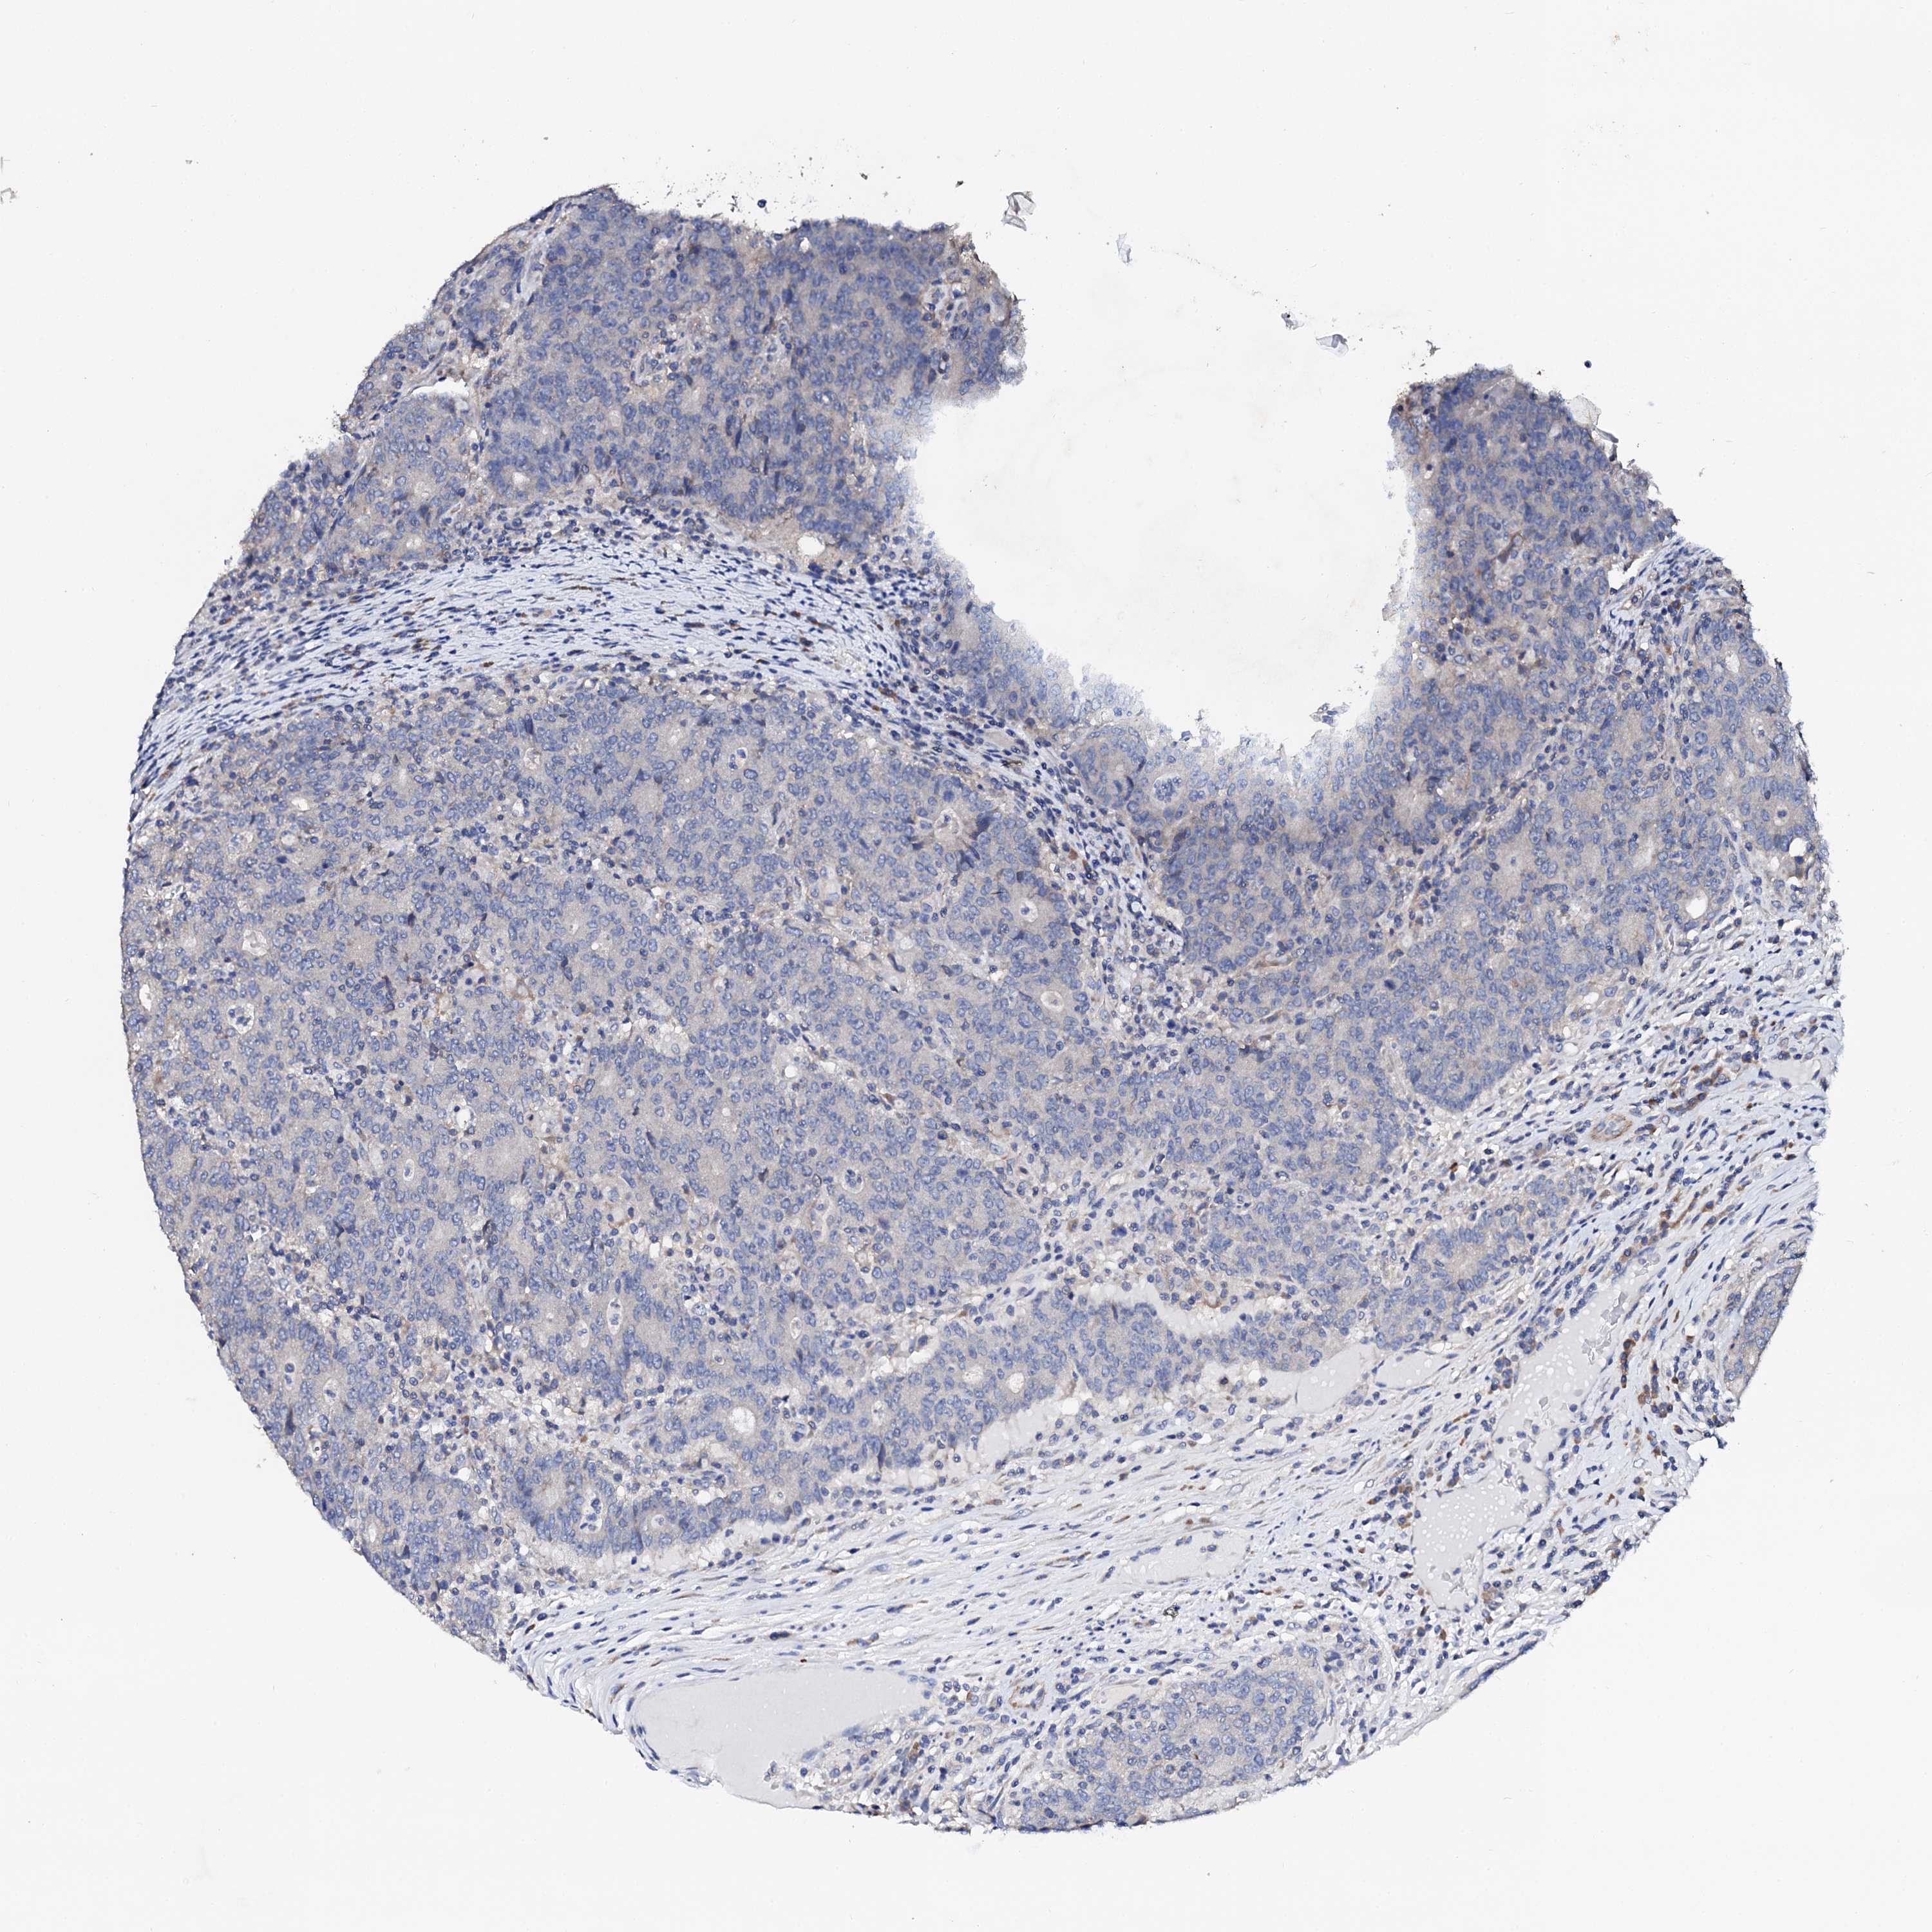

CANCER COLORECTAL CANCER Show tissue menu

Colorectal cancer

Human cancer

Colon adenocarcinoma

NUP58 is not prognostic in Colon Adenocarcinoma (TCGA)